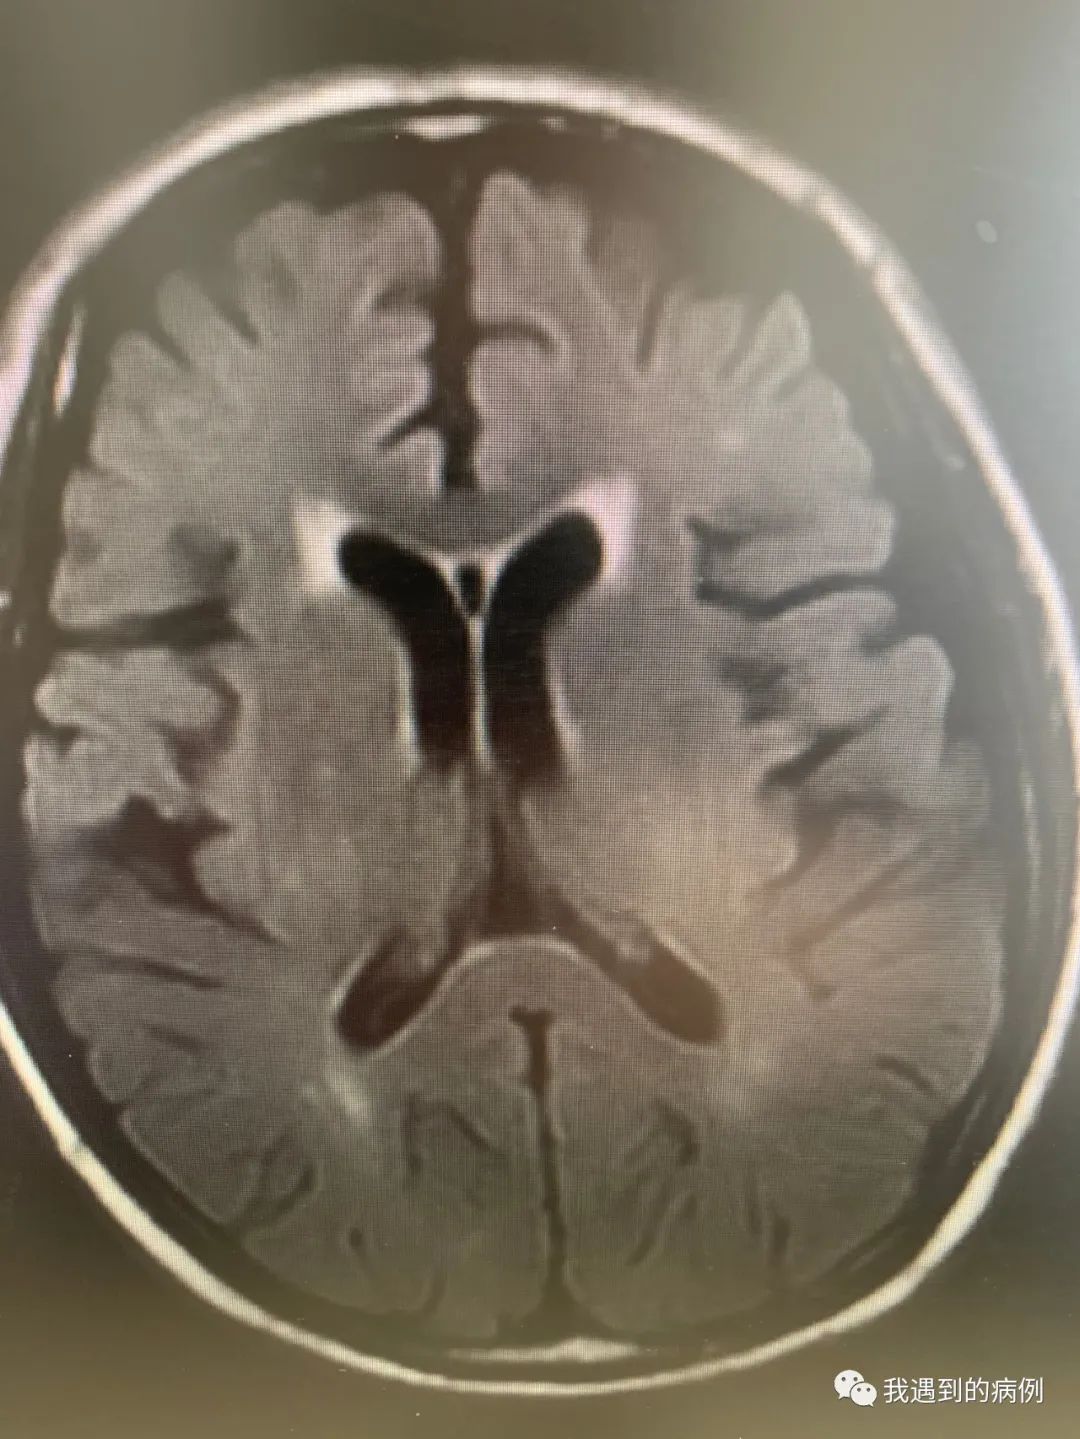

23.6.15头颅MRI抑水相示脑内斑片状多发病灶,累及中脑、脑桥,双侧颞叶内侧面,丘脑、基底节区及幕上白质,弥散无明显高信号灶。而23.5.23兄弟科室头颅MRI平扫相对干净。因此这些病灶即责任病灶。

23.5.23相对正常的头颅MRI

23.6.15发病时影像